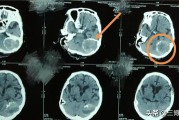

在颅内肿瘤中,脑膜瘤很常见,占颅内肿瘤的19.2%。发病以成人多见,儿童较少,女性多于男性。脑膜瘤原发于蛛网膜内皮细胞,颅内蛛网膜颗粒与蛛网膜绒毛分布较多之处,都是脑膜瘤的好发部位。脑膜瘤在颅内分布很...